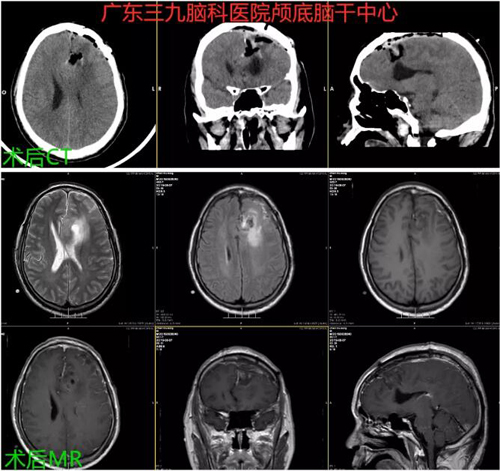

图2:术后CT及MR示左侧额部-镰旁占位性病变切除术后改变,原占位性病变已切除